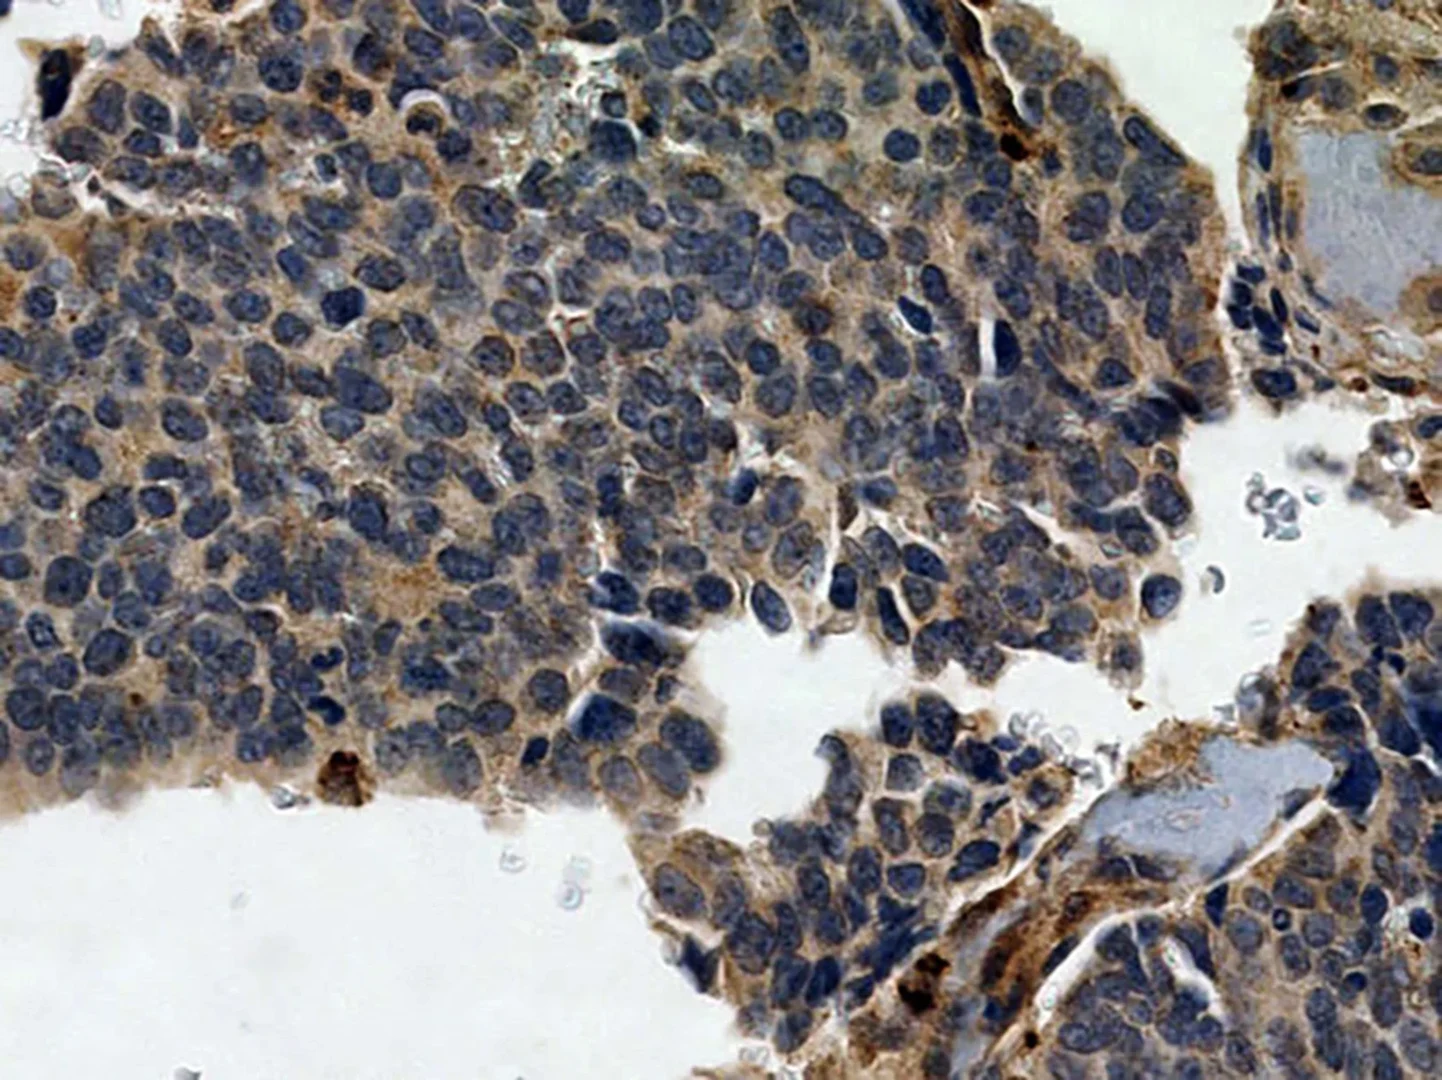

Prostatakarzinomzellen

Prostatakarzinomzellen - mit Nachweis des Neuropilin-2-Proteins in braun. Der Nachweis erfolgte über Immunhistochemie an Formalin fixierten und in Paraffin eingebetteten Gewebe. © Muderslab